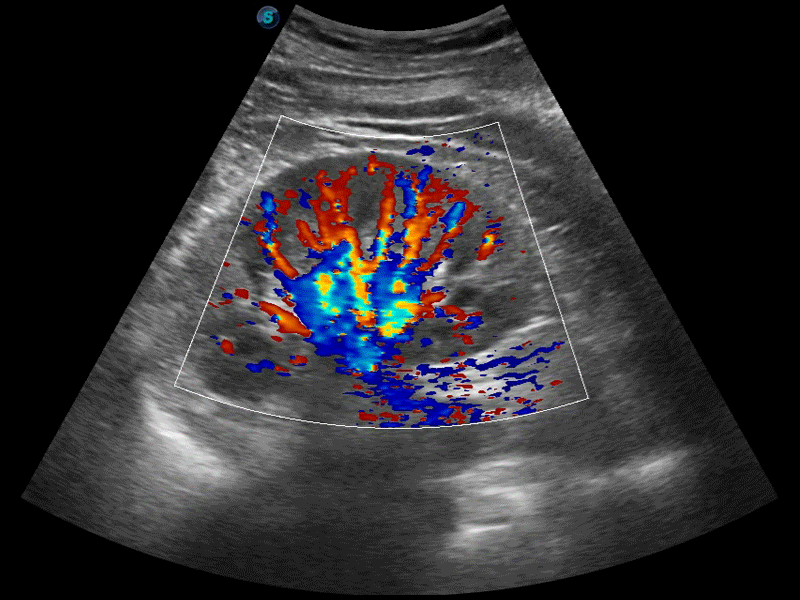

高分辨率血流成像技術提高了對低速血流信號的檢測能力。在提高空間分辨率的同時,也克服了血流外溢現(xiàn)象,為用戶提供更加真實的血流動力學信息。

凸陣、線陣和相控陣探頭進行實時掃描時,開啟擴展成像模式,可以擴展超聲圖像視野,以便更完整地查看大的病灶或組織器官的解剖結構。

通過色彩血流和實時寬景相結合,可觀察到完整的靜脈或動脈的血流,方便醫(yī)生檢查。實時掃查過程中,如有任何操作失誤也可以很容易地進行回掃擦除,而不會中斷掃查。